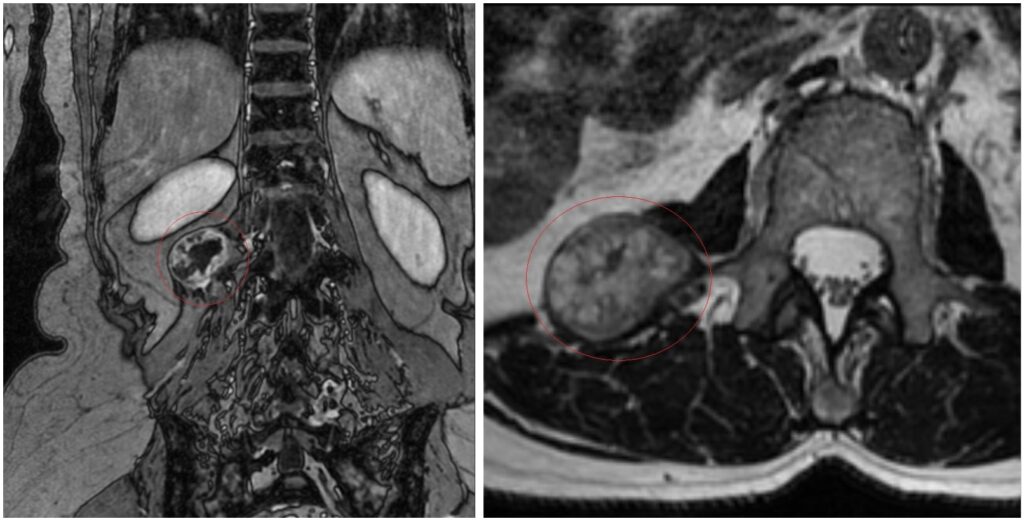

«По МРТ была диагностирована опухоль, предположительно, невринома, паравертебральной локализации. Только тогда я вспомнила, что ещё в 2018 году мне делали УЗИ органов брюшной полости и заметили небольшое образование около позвоночника. Оно меня никак не беспокоило и на время я о нём даже забыла. Затем стала болеть спина, тянуло в руке, в ноге, но я не связала эти факты между собой. Сейчас, когда сделали МРТ после обращения к травматологу, я вспомнила об опухоли. За это время она несколько увеличилась в размерах», — рассказывает Ирина Зайцева

Магнитно-резонансная томография выявила паравертебральное (расположенное рядом с позвоночным столбом) объёмное образование размером около 3×4х3 см на уровне L1-L2 позвонков справа. Пациентка обратилась к врачу-нейрохирургу ННИИТО им. Я.Л. Цивьяна.

«Новообразование требует хирургического лечения, причём в этом случае не нужно делать предварительную биопсию — опухоль локализована и имеет чёткие границы. Пациентка согласилась на оперативное лечение, после оформления документов на квоту приехала на госпитализацию в ННИИТО и была прооперирована. Мы осуществили малоинвазивный доступ к опухоли сзади, выделили образование и полностью удалили. Опухоль отправлена на гистологическое исследование, однако по всем признакам, с большой вероятностью это будет невринома — доброкачественная опухоль», — комментирует к.м.н., врач-нейрохирург Иван Пендюрин.